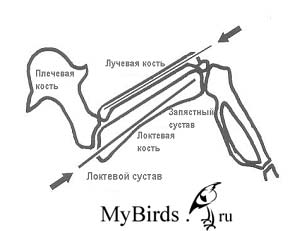

Интрамедуллярный остеосинтез локтевой и лучевой кости с помощью внутрикостной спицы. Рисунок C. Haupt

Нормальная анатомия скелета взрослого черного стрижа (плечевой пояс и крылья): 1) ключица, 2) клювовидный отросток, 3) лопатка, 4) плечевая кость, 5) лучевая кость, 6) локтевая кость, 7) пястно-запястная кость или пряжка, 8) фаланга придаточного крылышка , 9) короткая трубчатая кость и 10) дистальная фаланга большого пальца

Вывих локтя в срединно-боковом радиационном канале: полностью оторванная связка

Вывих локтя в каудально-краниальном канале |

Перелом лучевой кости, смещенный

Перелом лучевой кости после внутрикостной фиксации 0,4 мм канюлей |

Вывих запястья: в срединно-боковом радиационном канале. Повреждение выглядит незначительным и может остаться незамеченным

Вывих запястья: степень повреждения можно увидеть только с помощью каудально-краниального рентгеновского исследования |

Крыло расположено в физиологическом положении. Чувствительную к давлению растянутую кожу крыла (показано стрелкой) необходимо осторожно удерживать в пальцах. Рисунок: C. Haupt

Эластичная повязка накладывается снизу вверх вокруг плечевой кости, затем через плечевой сустав и вокруг запястья. Рисунок: C. Haupt

Повязка располагается дорсально через крыло, снова перетягивается крестообразно снизу и вдоль под плечевой костью. Рисунок: C. Haupt

Локтевая кость фиксируется в противоположном направлении; здесь спица выходит, будучи максимально согнутой, из проксимального конца локтевой кости прямо под локтевым суставом. Можно использовать 0,5 мм канюлю или спицу для скелетного вытяжения. Предосторожность: локтевой сустав может окостенеть! Наиболее благоприятным для лучевой кости является медиальный доступ, а для локтевой кости – дорсальный.